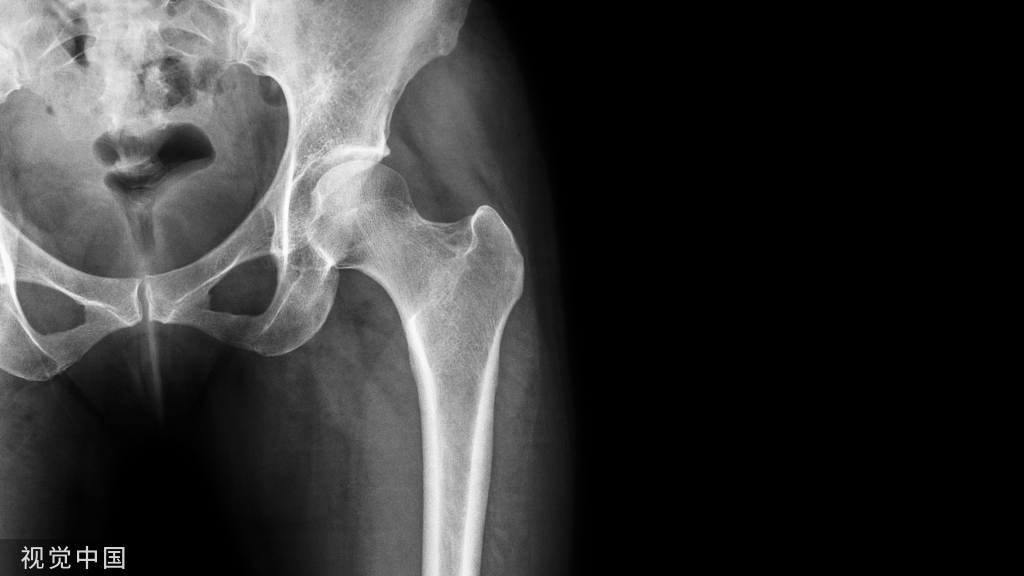

3、X线影像

髋关节正位和蛙式位是诊断股骨头坏死的X线 基本体位,通常在早期表现为硬化、囊变及“新月征”,坏死区与正常区域之间往往可见硬化征象等;晚期股骨头因塌陷失去原有球面结构,以及呈现退行性关节炎表现。